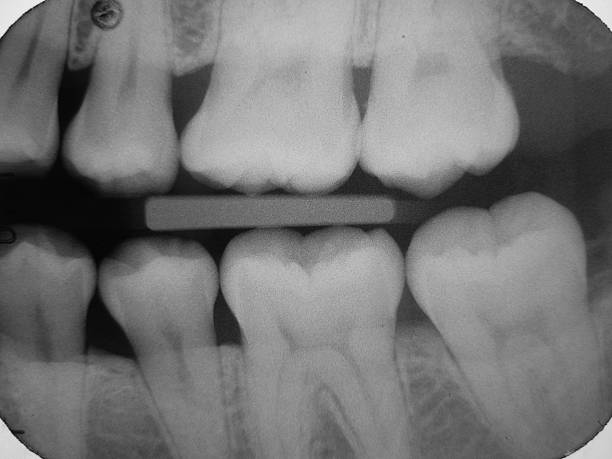

そのためにむし歯の進行度の判断材料となるデンタルX線写真を撮影します。

特に『咬翼法』のむし歯検出率は高く、60%程度と言われています。

それでも60%ですので、

他の診断方法も併用して総合的に判断する必要があります。

また、非切削治療の効果が出ているか、X線写真や視診で定期的に評価してく必要があります。